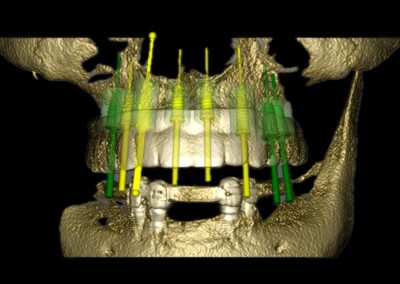

Vor der eigentlichen Operation können Implantatpositionen sorgfältig festgelegt werden, wobei spezifische Faktoren wie das Knochenvolumen und die -qualitäten, die Lage anatomischer Strukturen (wie Nerven, Gefäße und Nebenhöhlen), prothetische und ästhetische Bewertungen sowie präzise Messungen der Breite und Höhe des Knochens an den vorgesehenen Implantatstellen berücksichtigt werden. Auch die Abstände und Winkel zwischen den Implantaten lassen sich exakt berechnen, was entscheidend für den langfristigen Erfolg der Behandlung ist.

Ein weiterer Vorteil dieser Technologie ist die Möglichkeit der dreidimensionalen Positionierung der Implantate, die entscheidend für optimale klinische Ergebnisse ist, insbesondere in Bezug auf ästhetische Gesichtspunkte. Die geführte Implantatchirurgie (GIS) ermöglicht es, vorher geplante Rehabilitationsprojekte direkt und präzise in das chirurgische Feld zu übertragen. Dies fördert nicht nur die Genauigkeit, sondern kann auch dazu beitragen, eine minimal-traumatische oder lappenlose Operation durchzuführen.

Darüber hinaus erlaubt die GIS eine optimale Positionierung der Implantate und schafft die Voraussetzungen für eine sofortige Belastung. Dadurch wird nicht nur der Komfort des Patienten erhöht, sondern auch die Notwendigkeit von postoperativen Behandlungen und Schmerzen verringert.

Bilder v.l.n.r.: 01 Herstellung der röntgenopaken Schablone zur Übertragung auf den Dicom-Datensatz / 02 Planung der Zahnimplantatstellung anhand der röntgenopaken Schablone / 03 Virtuelle Planung auf dem 3D-Modell / 04 Übertragung der Röntgenschablone auf dem Dicom-Datensatz (1:1) / 05 Virtuelle Plaung im Dicom-Datensatz / 06 Visualisierung frontal / 07 Visualisierung seitlich / 08 Visualisierung des Implantat-Falles frontal / 09 Visualisierung mit Bohrschablone

3. Simulation und chirurgische Umsetzung

Moderne Planungssoftware erlaubt:

• Virtuelle Implantatinsertion

• Kollisionsanalysen

• Simulation augmentativer Maßnahmen

• Planung navigierter oder schablonengeführter Chirurgie

Die digitale Planung kann direkt in eine CAD/CAM-gestützte Bohrschablone überführt werden, wodurch die intraoperative Umsetzung hochpräzise erfolgt.